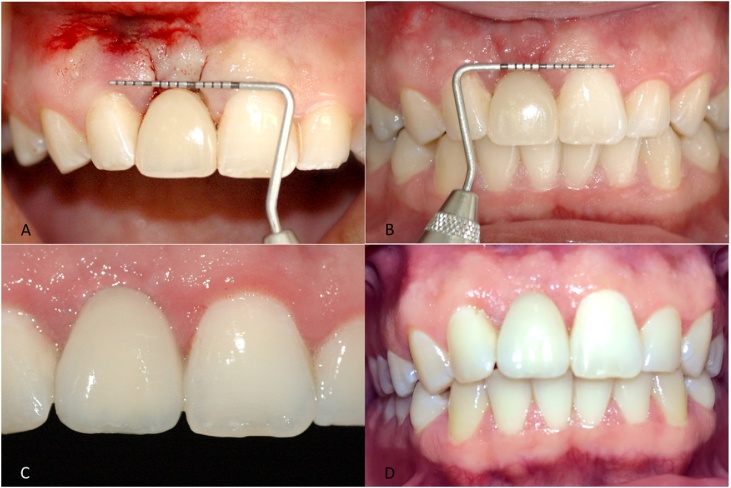

In a later appointment, an acrylic resin shell (Duralay) was manufactured in the mouth over the intermediate abutment for later melting into a coping for the implant-supported crown. Periodontal surgery started after adjustments of the provisional crown. The operator, with previous experience in periodontal surgical techniques, selected an adaptation of the pinhole periodontal procedure [10] and of the technique proposed by Tarnow [11]. Initially, the patient was anesthetized with articaine 4% + epinephrine 1:100,000 (DFL®, Rio de Janeiro), and then two horizontal 2-mm incisions were made, separated by 3 mm of intact gingival tissue, using blade #15 in the alveolar mucosa, close to the top of the implant (Fig. 4A). A curved papilla elevator was inserted at the incision sites, dislodging the mucogingival flap. Flap elevation was guided by visualization of the shape and movements of the instrument through the mucosa and the gingival tissue, keeping them intact without fenestration. Detachment was then extended coronally and horizontally in order to elevate the papillae around the implant. The gingival implant in the region of the alveolar ridge was preserved without any rupture. The interproximal extension of the flap allowed free movement, permitting its coronal repositioning, extending it beyond the crown-implant interface. The distinctive feature of the pinhole procedure [10] was observed at the time of flap stabilization. In that technique [10], the gingival flap is stabilized using a malleable, bioresorbable membrane with no need of sutures. When compared with the technique proposed by Tarnow [11], which uses a semilunar incision, the current technique with two 2-mm incisions is aimed at reducing the surface area of the incision, allowing for larger vascularization of the flap at all times, which may improve healing of soft tissues later on. After detachment of gingival tissues, making them flabbier, the flap was stabilized using horizontal mattress suture (nylon 4.0) through the incision site with the knot tied in the palatal gingiva, thus preserving the gingival papillae (Fig. 4B). At the end of the procedure, the patient was informed about the postoperative protocol, which included specific care for the manipulated region, and about the use of medications (antibiotic and anti-inflammatory drugs). The gingival mucosa was assessed using a periodontal probe moved horizontally (Fig. 5A).

Fig. 4.

4A – Horizontal incision in the alveolar mucosa; 4B –Gingival repositioning with combination of Tarnow’s and pinhole surgical techniques.

Fig. 5.

5A – Confirmation of gingival position after periodontal surgery. The papillae were preserved; 5B –10 days after surgery showing healthy gingival tissue without gingival recession; 5C –Final clinical aspect after 3 months; 5D – Final clinical aspect after 19 months.

A graduated periodontal probe was used for patient evaluations. After 10 postoperative days, the gingival tissue showed satisfactory healing, with no signs of recession, infection, or inflammation, and no intercurrent events (Fig. 5B). After 3 months, there was remarkable improvement of gingival retraction, the peri-implant tissues were healthy, and gingival morphology was appropriate. In addition to gingival alignment with the adjacent teeth, the gingival papillae properly filled the interdental spaces (Fig. 5C). In the follow-up visit at 19 months, the peri-implant tissues were healthy without gingival retraction, and the morphology was preserved, with presence of keratinized gingival tissues along the anatomic shape of the prosthetic rehabilitation (Fig. 5D). At the end of treatment, the patient seemed satisfied with the esthetic outcome.

To improve gingival esthetics in these cases, subepithelial connective tissue grafting techniques are often necessary [15,16]. To avoid an extensive surgical procedure, two techniques were used: the pinhole surgical technique [10], in which the gingiva is repositioned without the use of grafts; and Tarnow’s technique [11], in which a semilunar incision is made in soft tissues. After the healing period, there was considerable improvement in the gingival margin (Fig. 5D).